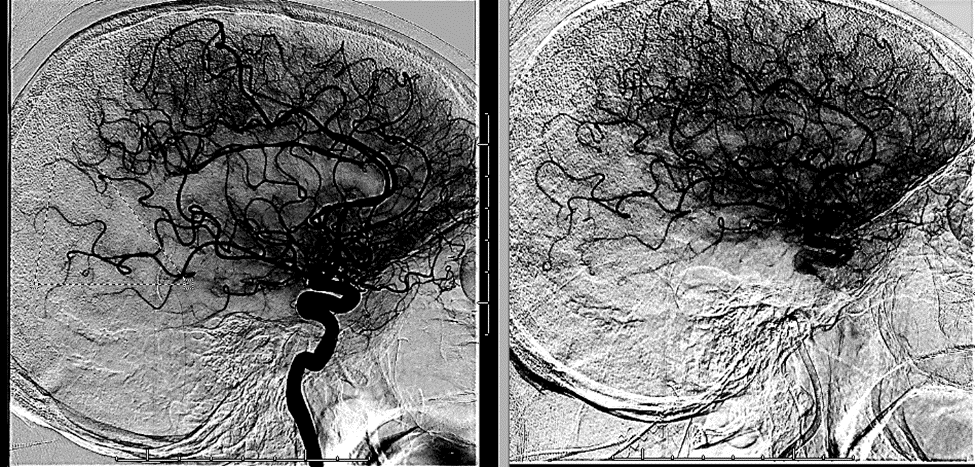

15/ The patient is kept in the ICU and ultimately undergoes #angiogram. Notice the area of perfusional deficit along the posterior MCA division:

16/ With some mild suction, @sudhakar_satti is able to suction a rubbery clot and the MCA looks much better post-procedure ๐Ÿ˜Ž

17/ The patient ๐Ÿšซ symptomatic recurrence since then! We suspect that the patient was intermittently occluding her anterior division with a fixed posterior division stenosis, and that is what was causing her symptoms: a ball-valve type phenomenon!